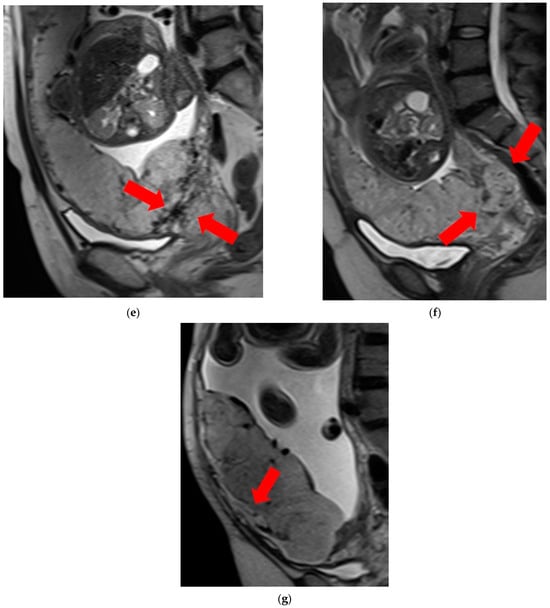

- T2 dark bands: dark lines on T2-weighted images showing nodular or linear patterns from the uterus to the placenta (Figure 1a).

Figure 1. Examination of magnetic resonance imaging features in the spectrum of placenta accreta with placenta previa disorder reveals the following characteristics: (a) T2 dark bands, indicating areas of low signal intensity on T2-weighted images (arrows). (b) Placental heterogeneity, depicting varied signal intensity within the placenta due to recurrent hemorrhages or lacunae (arrows). (c) Placental bulge, characterized by the protrusion of the lower segment of the uterus caused by the mass effect of the placenta, typically towards the bladder (arrow). (d) Placental cervical protrusion, showcasing the extension of placental tissue into the cervical canal (arrow). (e) Abnormal vascularization of the placental bed, featuring noticeable vessels in the placental bed with disruption of the uteroplacental interface (arrows). (f) A focal exophytic mass, indicating the protrusion of placental tissue through the uterine wall and beyond (arrows). (g) Myometrial thinning, demonstrating a reduction in myometrial thickness over the placenta to <1 mm or even making it invisible (arrow). - Placental heterogeneity: uneven signal intensity observed inside the placenta, often due to repeated bleeding (Figure 1b).

- Placental bulge: lower uterine protrusion caused by the placenta, usually toward the bladder (Figure 1c).

- Placental cervical protrusion sign: placental tissue sticking to the cervical canal (Figure 1d).

- Abnormal vascularization of the placental bed: disturbed blood vessels in the placental bed affecting the uteroplacental connection (Figure 1e).

- Focal exophytic mass: placental tissue extending through the uterine wall (Figure 1f).

- Myometrial thinning: Thinning of the uterine muscle over the placenta, sometimes becoming nearly invisible (Figure 1g).